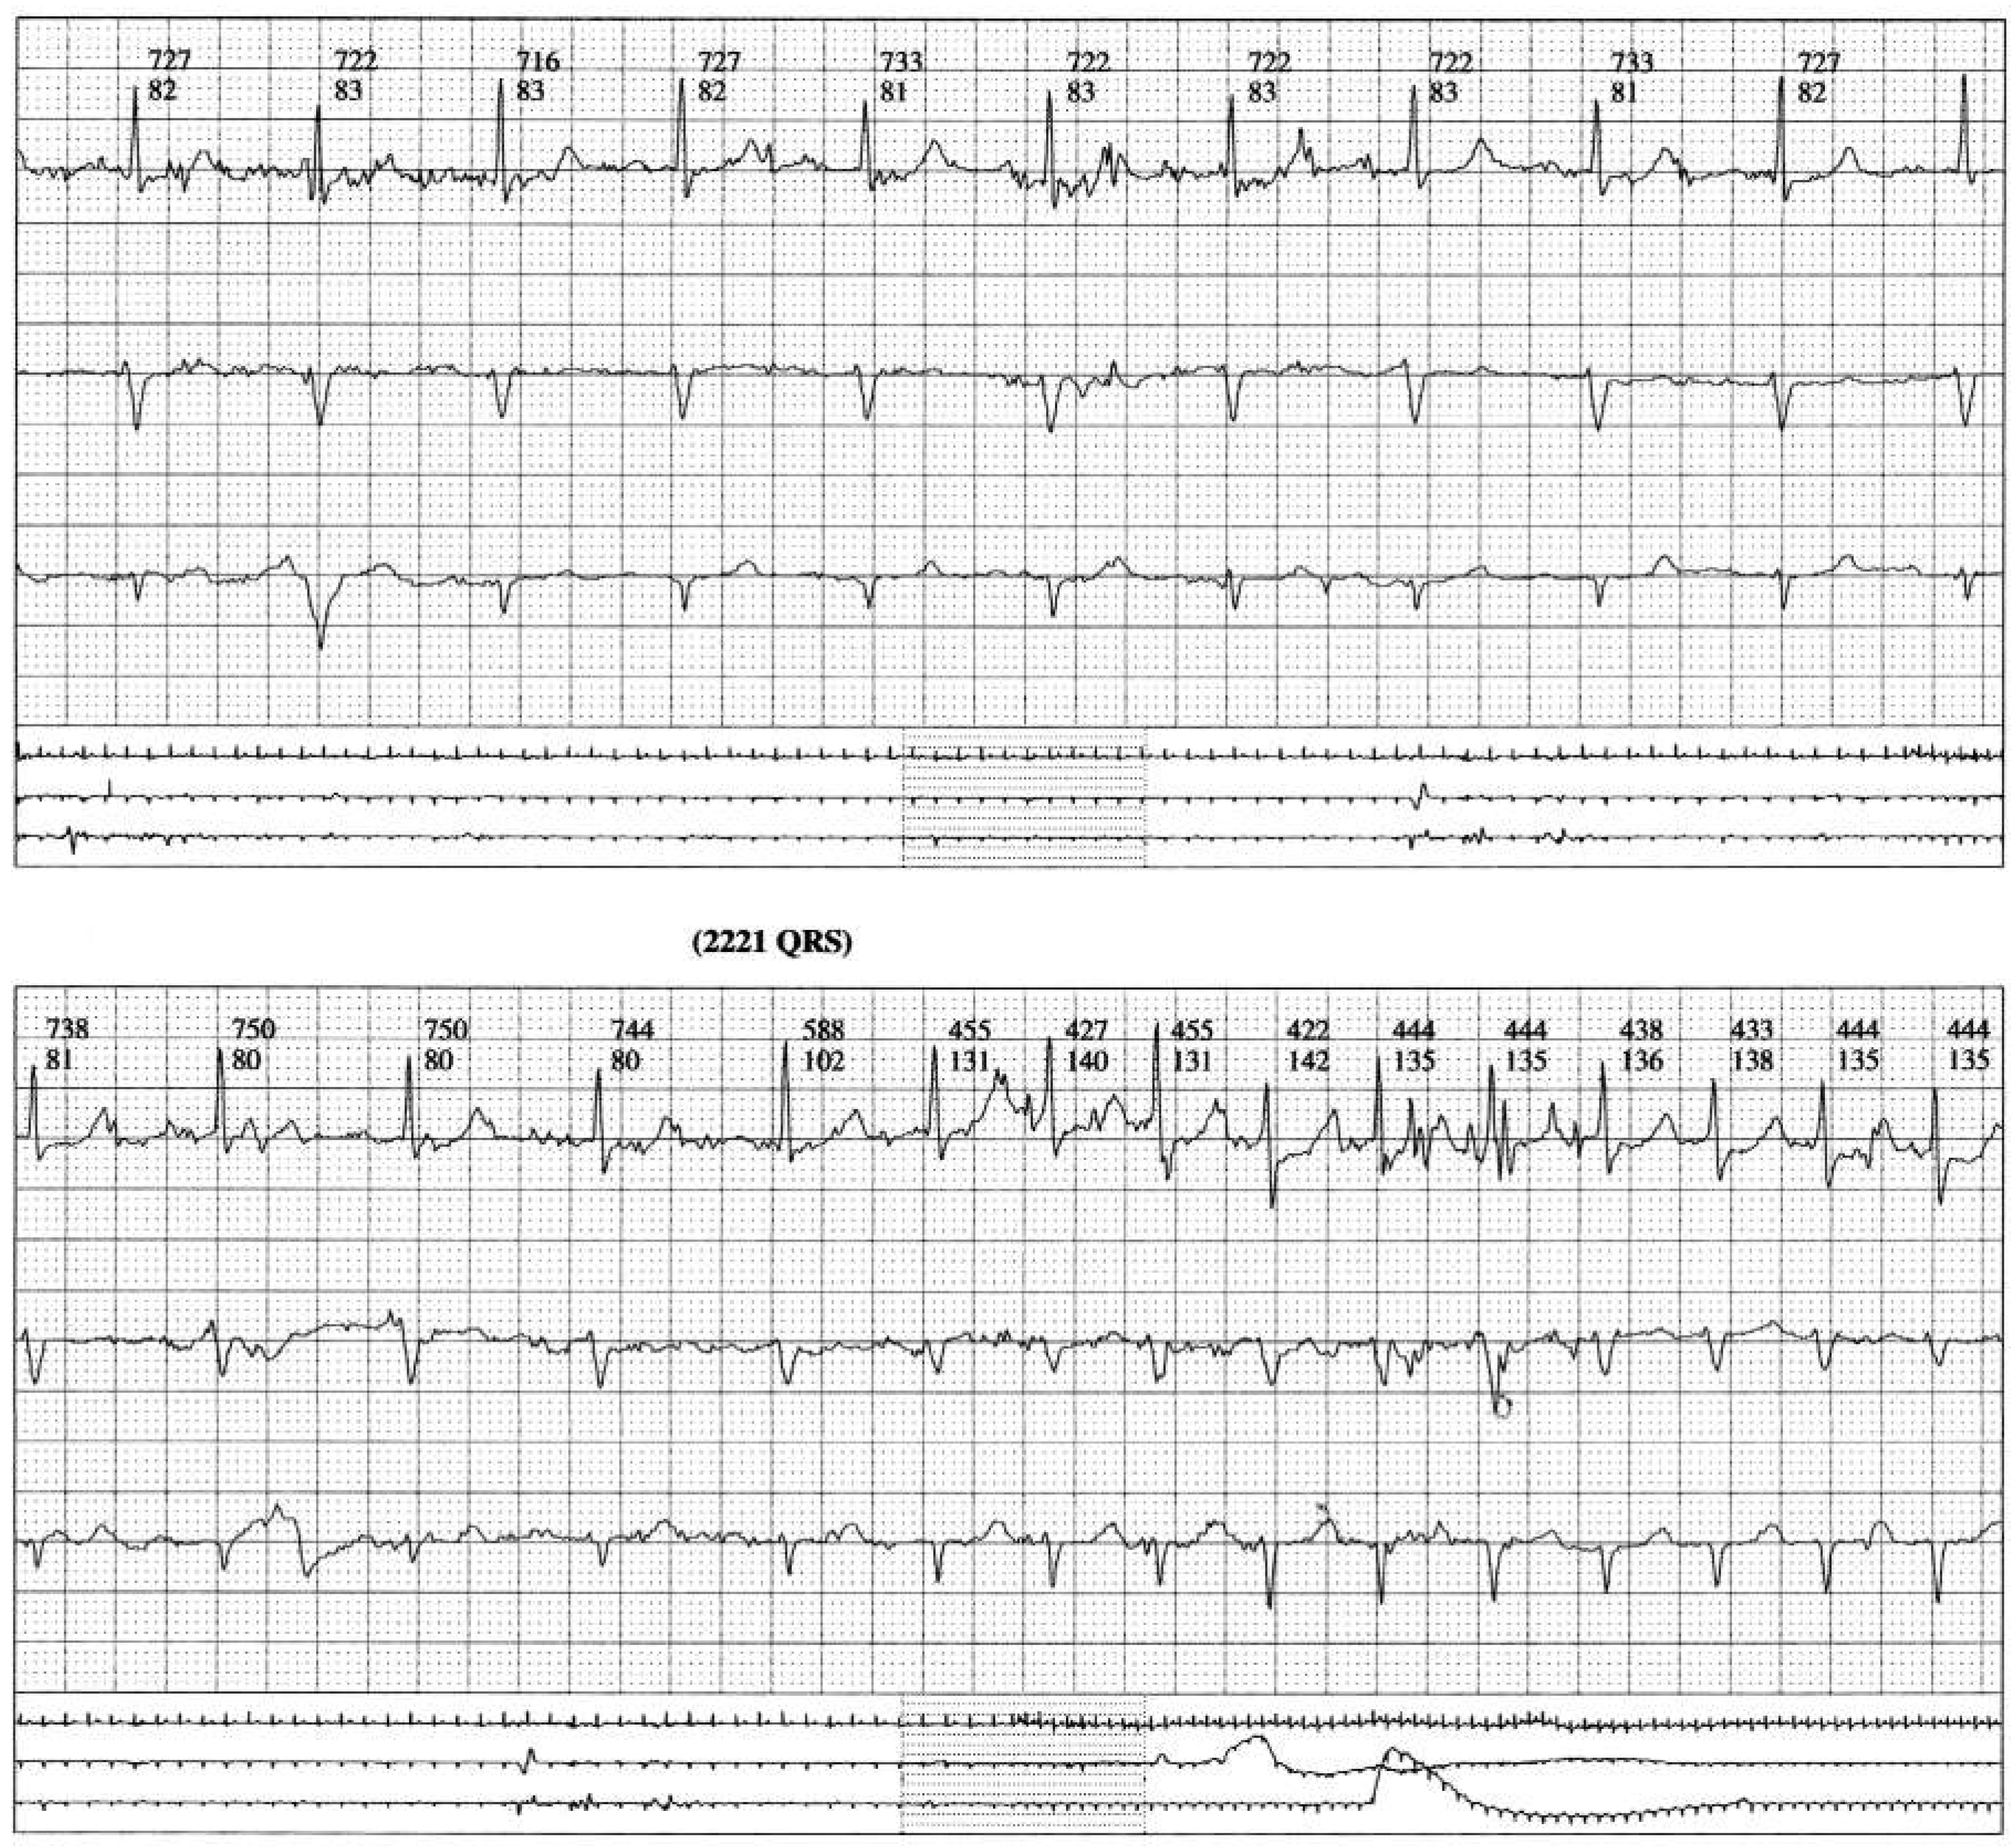

Figure 1b.

Dynamic ECG recording during jogging. Change from atrial arrhythmia to paroxysmal atrial fibrillation.

Figure 1c.

Dynamic ECG recording during jogging. Paroxysmal atrial fibrillation.

Figure 1d.

Dynamic ECG recording during jogging. Termination of atrial fibrillation.